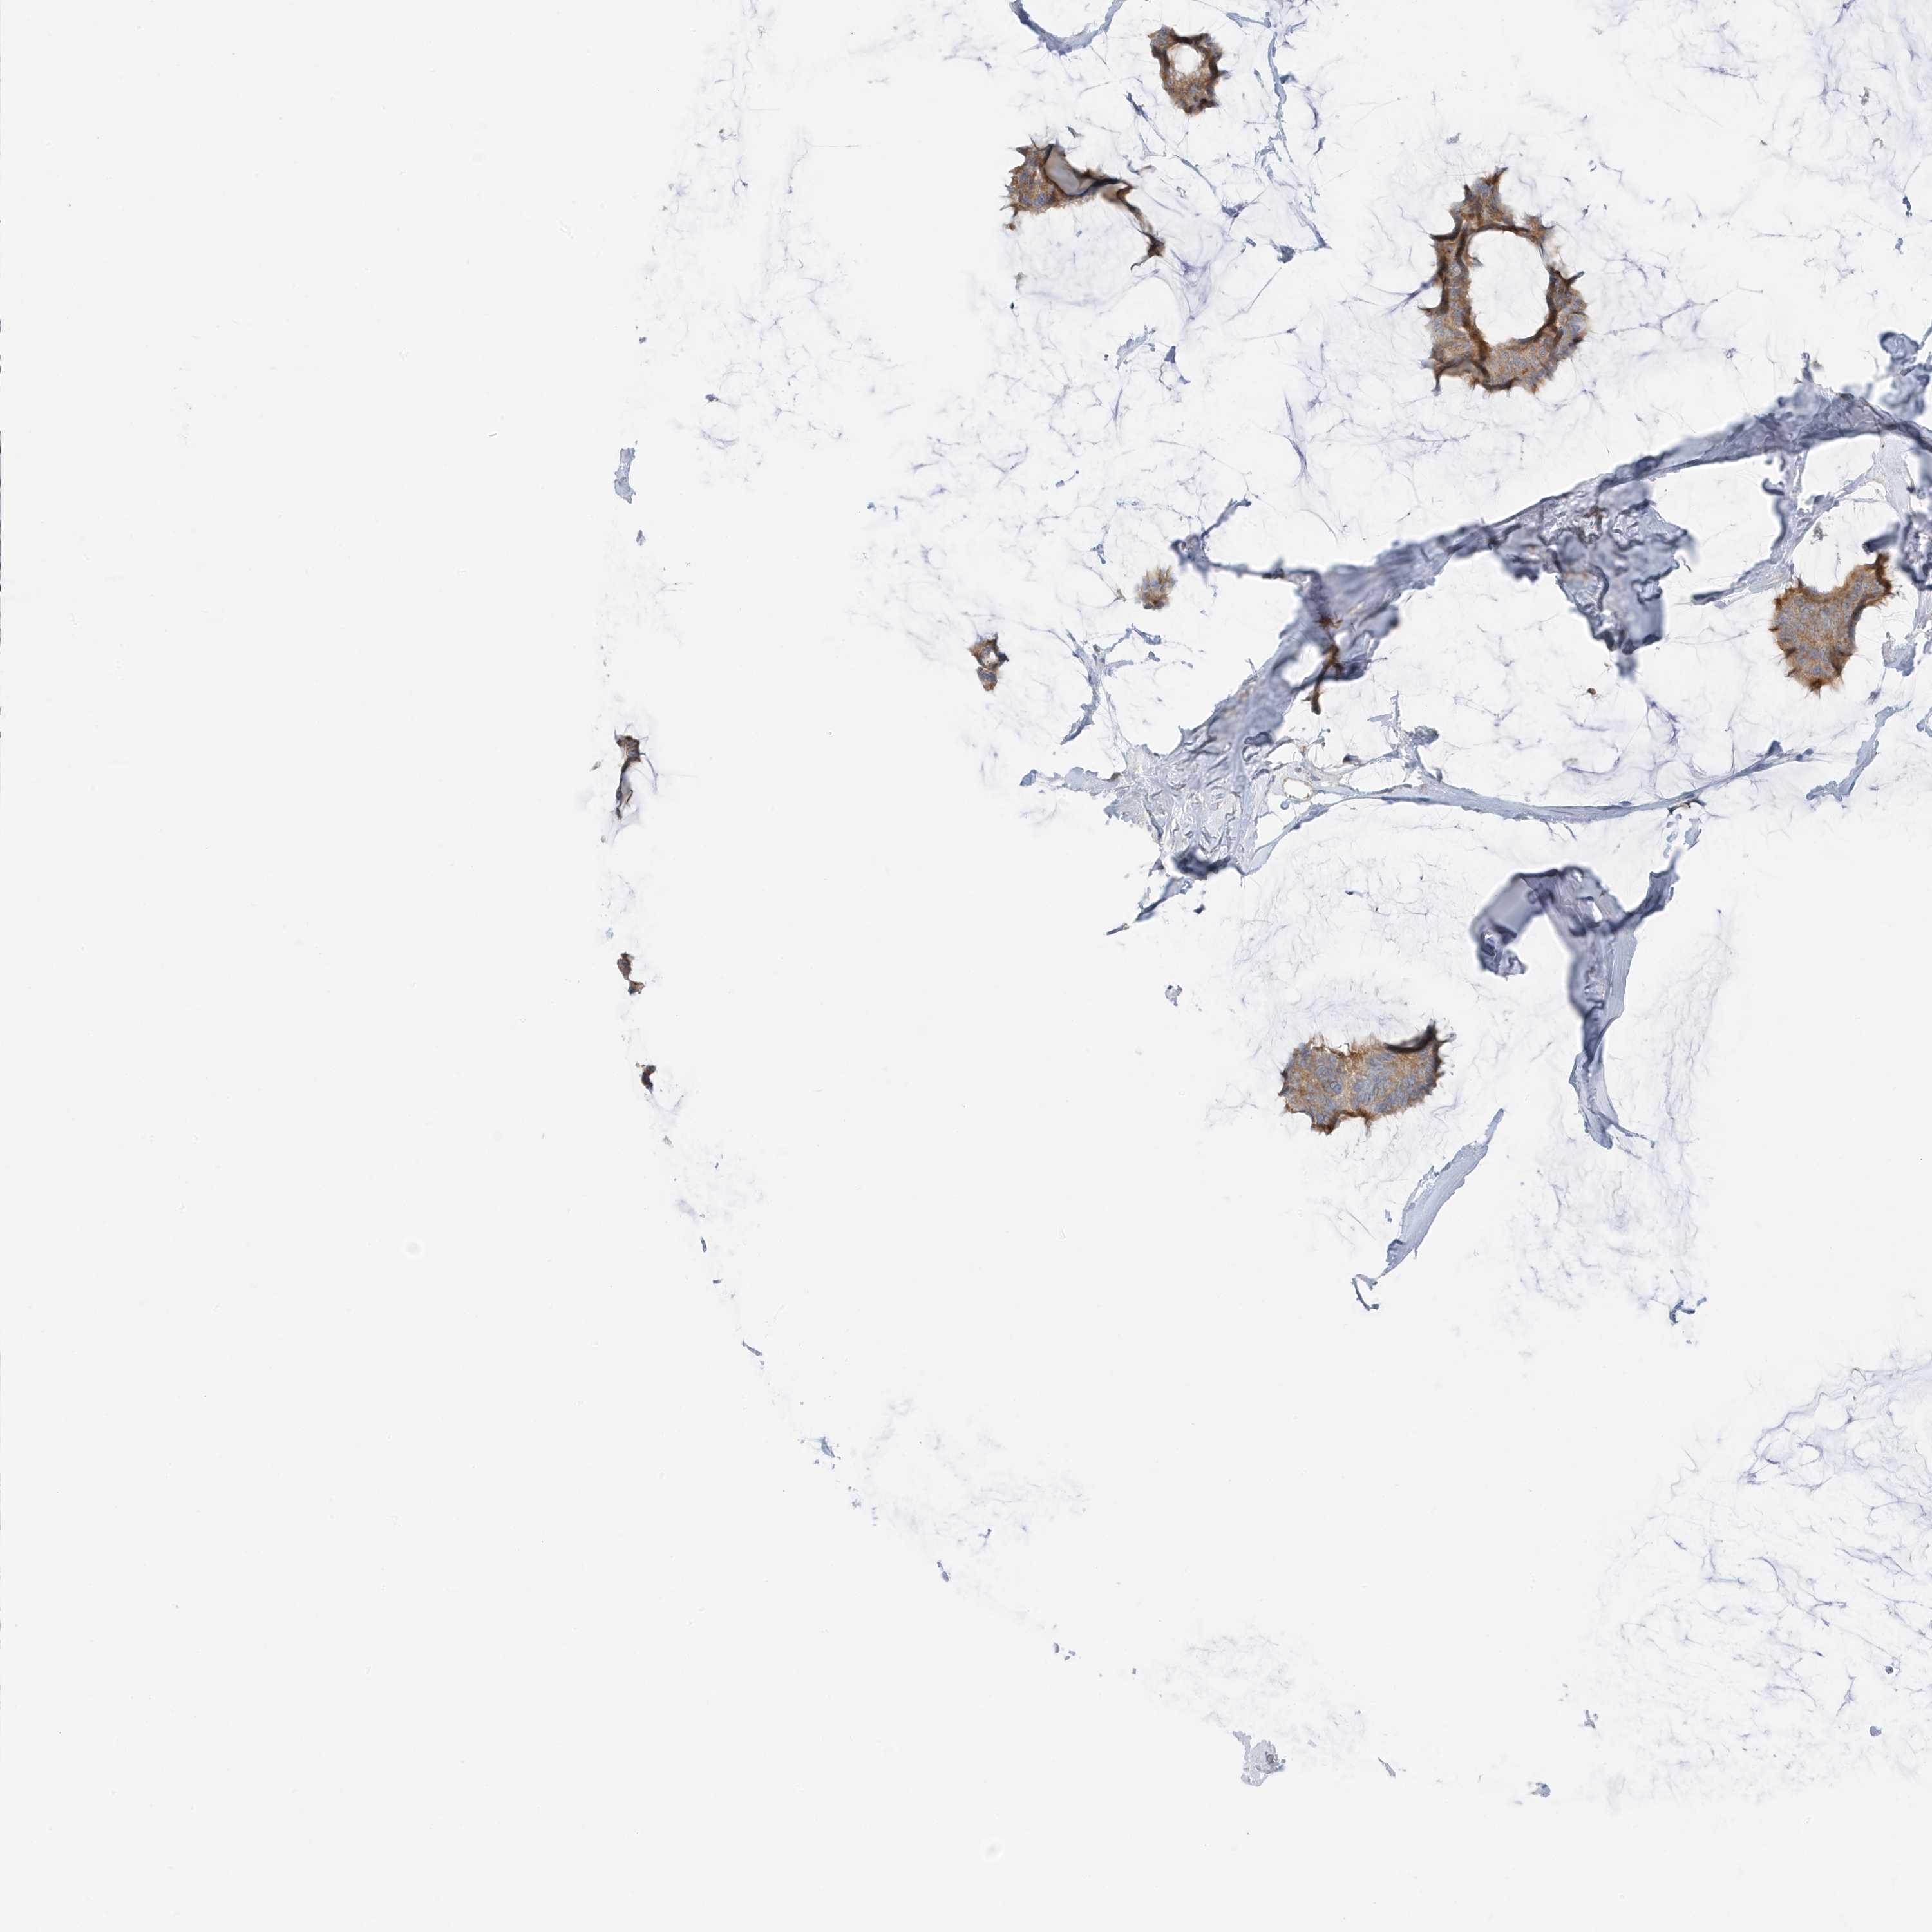

CANCER BREAST CANCER Show tissue menu

BRCA TCGA BRCA VALIDATION PROTEIN EXPRESSION